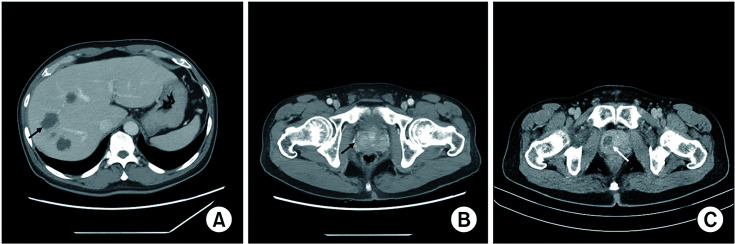

Abstract Image